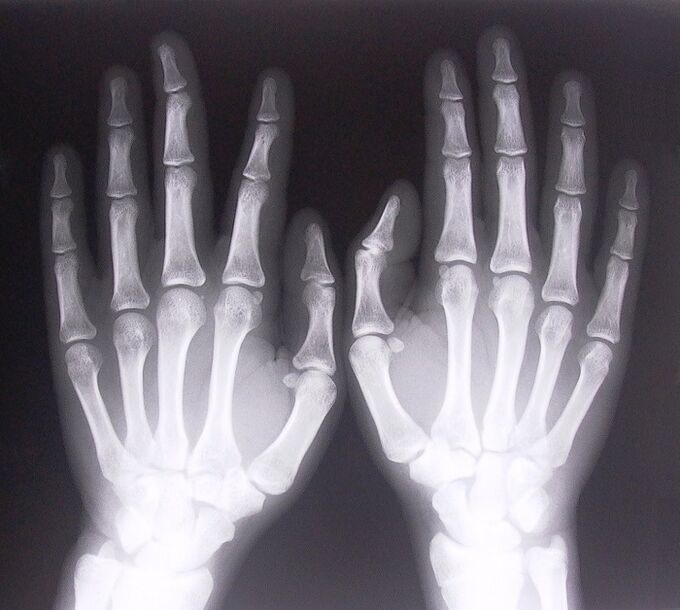

Pour commencer à traiter les douleurs articulaires des doigts, vous devez déterminer correctement quelle maladie les a provoquées. Pour déterminer le type de maladie dont souffre une personne qui ressent des douleurs dans les articulations en pliant les bras, les médecins recommandent les procédures suivantes :

- Prenez des radiographies.